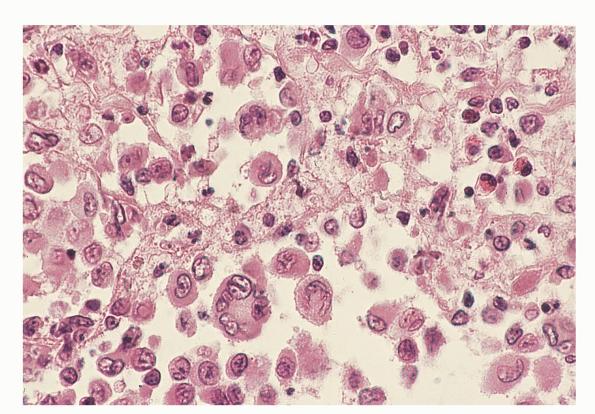

Langerhans cell histiocytosis = كثرة الخلايا الناسجة لانغرهانس